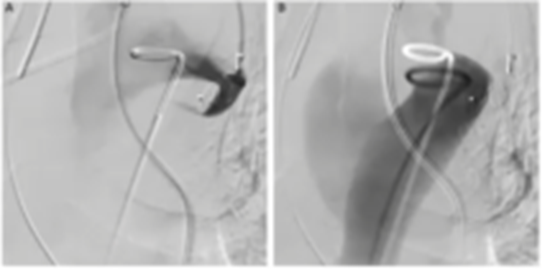

临床医师对Ⅱ型内漏的关注逐渐提高。Ⅱ型内漏的危险因素包括粗大通畅IMA(直径≥2.5 mm)、≥2条腰动脉、瘤腔长度和直径、髂总动脉长度等。目前,对于髂内动脉地处理,比较统一,无非是直接覆盖、栓塞和重建。现有的数据表明,直接覆盖并不能替代栓塞。另外,受解剖限制,IBD/IBE仅适用于约40%的CIA动脉。不仅如此,应用IBD/IBE会增加患者的经济负担,同样不适用于所有患者。受限于疾病本身、器具、技术以及费用等,栓塞ⅡA往往是预防Ⅱ型内漏的最佳选择。

多项研究表明,当通过血管内入路治疗解剖上具有挑战性的主髂动脉瘤疾病时,髂内动脉的栓塞往往是必要且安全的。栓塞髂内动脉不仅是一种安全有效的治疗方法,还增加了腔内修复主髂动脉瘤的适用性。2014年,一项回顾性研究评估2002~2011年间88例在EVAR术前接受了ⅡA栓塞的患者。ⅡA栓塞技术成功率为95.7%,术后38%出现了臀性跛行,10%勃起功能障碍,但无严重臀部缺血并发症。对比单侧和双侧栓塞、同时和分期栓塞,并无统计学差异。在大多数病例中,ⅡA栓塞术是安全有效的,可以防止显著的Ⅱ型内漏。2016年,一项评估EVAR术前栓塞ⅡA盆腔缺血发生率和相关因素的研究,共纳入25例患者,8例(32%)出现新发缺血,包括勃起功能障碍(4%)和臀部跛行(28%),仅4例(16%)持续6个月。进一步分析显示双侧ⅡA栓塞和较短的EVAR时间间隔与风险增加相关(P=0.006和P=0.044)。由此表明,ⅡA栓塞是一种有益的手术,为了最小化臀部跛行的风险,建议不要双侧ⅡA栓塞,适当延长与随后EVAR的时间间隔。2020年,一项纳入了139例主髂动脉瘤患者的回顾性研究,结果表明在EVAR行ⅡA栓塞是安全有效的,大多数患者为未发生(60.0%)或轻度(36.7%)臀部跛行。同年,一项对比ⅡA保留和栓塞疗效的回顾性研究,结果表明ⅡA栓塞技术成功率为100%,ⅡA栓塞常见并发症为臀肌跛行,仅1例ED,无其他严重并发症。4、AVP栓塞ⅡA是一种安全便捷且高效的方法,优于弹簧圈AVP作为栓塞装置,可以促进血液凝固,并对血流形成一道物理屏障,激活机体的免疫系统反应,从而启动机体的自身凝血过程。相较于弹簧圈,AVP是一种可以在高流量血管进行锚定的栓塞材料,更加均匀且致密。

2016年,一项多中心研究分析了2007~2013年间169例接受AVP治疗的临床疗效;研究结果,技术成功率为97.6%,手术平均时长14 min,平均需要1.43个AVP实现栓塞。随访期间未观察到ⅡA再通,证明了AVP的安全性。另外,一项弹簧圈和AVP的对比研究提示,AVP的手术和放射暴露时间更短(59 min vs. 97 min),使用数量更少(1.14 vs. 7.54),治疗成本更低。

另一项对比AVP和弹簧圈栓塞术后并发症的研究,结果显示总的并发症风险较低,常见的是臀部跛行(9.4%)、腹股沟血肿(1.1%)、内漏(5.3%)和勃起功能障碍(1.0%)。而无论是单侧,还是双侧ⅡA栓塞,AVP组臀肌跛行和勃起功能障碍的发生率都低于弹簧圈组。这可能是由于AVP定位准确,不会发生移位,集中于髂内主干,而弹簧圈可能会发生移位,导致栓塞髂内动脉壁支或脏支。此外,AVP成像伪影少,更容易识别可能发生的内漏,不影响EVAR术后影像监测的判断。

5、AVP栓塞ⅡA技术要点

一项纳入2,671例患者荟萃分析评估了ⅡA栓塞治疗对于患者后续的影响;结果表明,近端栓塞可以降低臀部跛行发生率,且AVP组比弹簧圈组并发症少,手术更便捷,造影更少。在两种栓塞技术都可行的情况下,优先考虑AVP,且栓塞尽可能位于ⅡA近端。